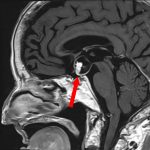

下垂体腫瘍

頭蓋内腫瘍摘出術

No.’25_114 手術前1

No.’25_114 手術前2